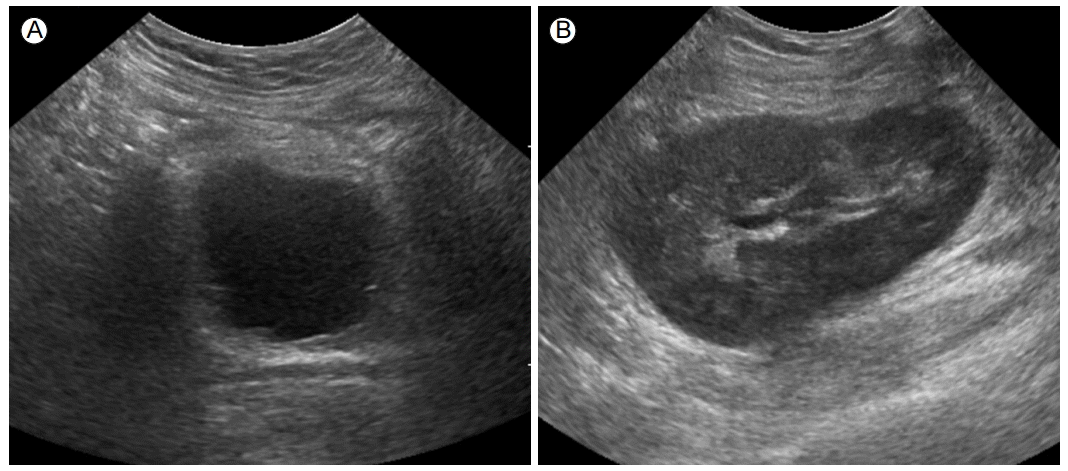

Figure 1.

Diffuse bladder wall thickening (A) and no abnormal echogenicity of the kidney (B) on ultrasonography.

한 달 전에 신이식 이후 외과에서 경과관찰하던 61세 여자가 당일 발생한 심한 배뇨통과 육안적 혈뇨를 주소로 응급실에 왔다. 고혈압에 의한 신질환으로 2년간 혈액투석을 하던 환자로, 뇌사자로부터 신이식(2 haplotype match; 4 of mismatch, cold ischemic time: 619분)을 받았으며 면역억제제(하루 tacrolimus 4 mg, mycophenolate mofetil [MMF] 1,500 mg, deflazacort 36 mg)를 복용 중이었다. 내원 당시 생체징후는 혈압 130/80 mmHg, 맥박 83회/분, 호흡수 20회/분, 체온은 36.8℃였다. 신체검사에서 이식 신 주위의 통증 및 열감은 없었으나 치골 상방으로 심한 압통이 있었다. 혈액 검사에서는 혈색소 12.7 g/dL, 백혈구 9,090/μL (호중구 73.0%, 림프구 19.0%), 혈소판 145,000/μL였다. 또한 혈중요소질소 24.2 mg/dL, 크레아티닌 0.99 mg/dL을 포함하여 간기능 및 전해질 검사의 결과는 정상이었다. C-반응단백은 0.34 mg/dL였다. 혈액 응고 검사(prothrombin time, activated partial thromboplastin time)는 정상범위였다. tacrolimus 최저혈중약물농도는 8.4 mg/mL였다. 소변검사 소견은 적혈구 > 100/고배율시야, 백혈구 51-100/고배율시야, 변형 적혈구 < 10이었다. 초음파 검사에서 이식 신에는 특이소견이 없었으나, 두꺼워져 있는 방광벽을 관찰할 수 있었으며(Fig. 1), 혈뇨 발생 5일 후의 혈색소가 9.5 g/dL까지 감소하여 grade 3의 출혈성 방광염으로 진단할 수 있었다. 초기 소변 배양검사에서 세균은 발견되지 않았고, 항생제를 투여(3세대 세팔로스포린)하며 1주일간 경과관찰하였으나 육안적 혈뇨 및 배뇨통이 지속되어 환자는 내과로 전과되었다. 추가로 시행한 소변의 아데노바이러스, 거대세포바이러스, 마이코플라즈마, 항산균 및 진균에 대한 검사는 모두 음성이었다. 또한 2회 시행한 뇨세포 검사에서 decoy cell은 발견되지 않았다. 그러나 polymerase chain reaction (PCR)을 이용한 소변의 BK 바이러스 정량검사에서 1,287,300 copies/mL의 바이러스가 검출되었다. 단, 혈액에서는 검출되지 않았다(< 700 copies/mL). 이에 BK 바이러스와 관련된 출혈성 방광염 진단 하에 MMF를 중단하였으며 tacrolimus는 최저혈중약물농도 6 ng/mL를 목표로 감량하였다. 그리고 ciprofloxacin 200 mg 하루 2회 정맥주사하였으나 치료 중에 초기에 없던 발열(38.5℃)이 발생하며 신기능 악화가 동반되었다(크레아티닌 1.6 mg/dL). BK 바이러스를 효과적으로 조절하기 위해 충분한 수액 공급과 더불어 leflunomide 부하용량(100 mg 3일)을 투여한 이후 유지용량(20 mg)을 투여하였다. 또한 재시행한 이식 신 초음파에서 이전에 없었던 수신증을 발견하였다(Fig. 2). 이식 신의 거부반응을 감별하기 위해 이식 신 조직검사를 시행하였고 호중구와 단핵구 침윤을 동반한 간질의 출혈과 괴사 소견을 동반한 interstitial inflammation score 3에 해당하는 심한 염증 소견은 볼 수 있었으나 거부 반응과 관련한 intimal arteritis나 peritubular capillaries의 C4d 침착은 찾기 어려웠다. SV40 면역형광염색에서 equivocal patch intratubular staining을 보였으나 전자현미경에서 바이러스 입자를 발견할 수는 없었다(Fig. 3). Ciprofloxacin과 leflunomide를 일주일간 투여 이후 소변의 BK 바이러스는 351,960 copies/mL까지 감소하였고, 환자의 주관적인 증상이 소실되었다. 소변검사 소견은 적혈구 0-2/고배율시야, 백혈구 3-5/고배율시야로 혈뇨가 호전되었고 신기능은 크레아티닌 0.96 mg/dL로 회복되었다. 2달 후, 신 초음파에서 수신증은 관찰할 수 없었다. 또한 조직검사에서 BK 바이러스는 발견할 수 없었고, 이전 조직검사에서 보였던 interstitial inflammation과 fibrosis를 여전히 관찰할 수 있었다(Fig. 4). 현재 요로계 관련 증상은 없으나 viruria는 지속되는 상태로 cyclosporine으로 면역억제제 변경 후 경과관찰 중이다.